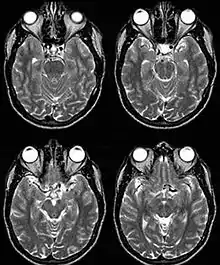

Internal carotid artery dolichoectasia is particularly interesting because the artery normally already contains one hairpin turn. Seen in an MRI as two individual arteries at this hairpin, a carotid artery dolichoectasia can progress so far as to produce a second hairpin turn and appear as three individual arteries on an MRI. In the case of a dolichoectasia of the Internal Carotid Artery (ICD), the pathogenesis is primarily related to compression of the optic nerves at the optic chiasma (see Fig. 1 and 2).